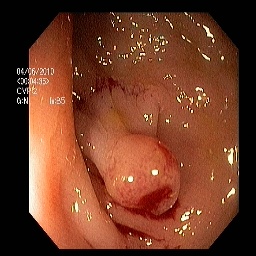

The performance metrics for Edgeconnect and AOTGAN on the validation data after fine-tuning the models, are shown in Table II. In addition to qualitative evaluation, Figure 3 provides example data from the different steps of the PolypConnect pipeline using the EdgeConnect model and the AOTGAN model. Due to obvious visual differences in the generated polyps between the models, we selected the EdgeConnect model as the main polyp inpainting model of the PolypConnect pipeline for further evaluation and qualitative assessment by domain experts.

Figure 3: Sample data used and generated in the different steps of PolypConnect pipeline. (a) - real polyp images, (b) - manually annotated polyp masks, (c) - randomly selected colon images used as input to the final step of PolypConnect, (d) - extracted edge images of row c. (e) - extracted edge images of polyp regions of row a using the masks of row b. (f) - combined edge images of row d and f. (g) - generated polyp on the images of row c using EdgeConnect. (h) - generated samples from AOTGAN.